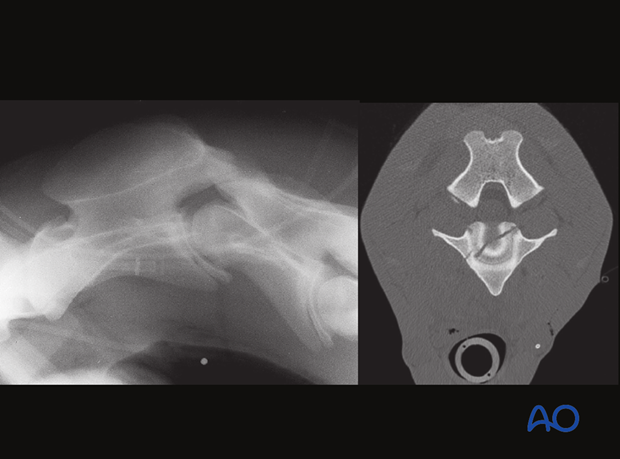

Fracture of the atlas vertebra.

Computertomography: